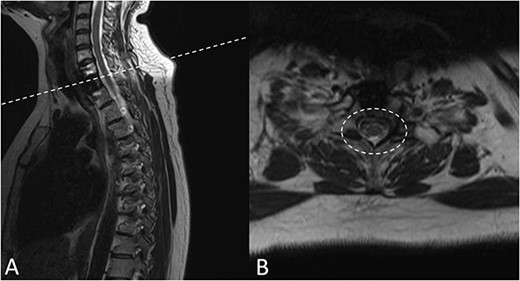

Preoperative magnetic resonance imaging (MRI) and preoperative CT scans helped determine Tokuhashi, Tomita and ESCC scores, which was vital to plan treatment for this patient (Figs 1 and 2). The occurrence of the lesion occurring in T2 indicated an anterior approach. This would be safer than a posterior approach as the ESCC grade of 2 made it surgically challenging to resect tumour and lay instrumentation around the spinal cord. An anterior approach also avoids cervico–thoracic junction fusion.

Preoperative CT Scan December 2019. Sagittal view of oligometastatic lesion at T2 vertebral body. (A) Sagittal view of oligometastatic lesion at T2 vertebral body. (B) Transverse view determined ESCC grade 2 as there is spinal cord compression, but with cerebrospinal fluid visible around the cord.